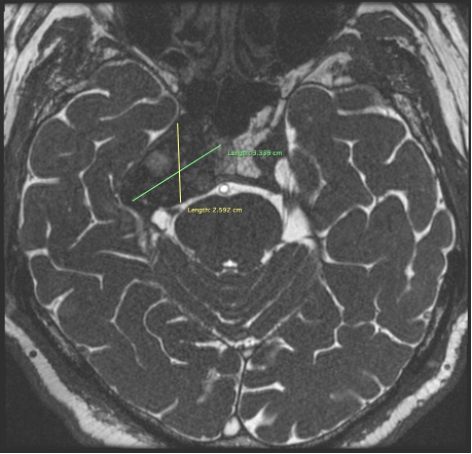

Results: Brain MRI (1,5 Tesla): MRI of the brain demonstrates a lesion in the right temporal bone region (squoma part) with mass effect on adjacent structures. The lesion measures (38х25х33 cm) and exhibits characteristics suggestive of a space-occupying process. Findings include: possible involvement of the brainstem and surrounding neurovascular structures, no evidence of acute hemorrhage, hydrocephalus, or significant midline shift.

Axial